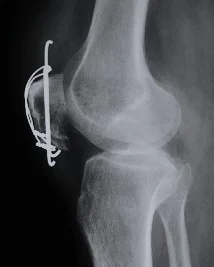

| Tension Band Wires | Special mechanics in – Patella – Olecranon – Malleolar fractures | ![]() |

External Fixation

- Indications in acute trauma:

- Fractures associated with severe soft-tissue damage (including open fractures) or those that are contaminated

- Fractures around joints that are potentially suitable for internal fixation but the soft tissues are too swollen to allow safe surgery

- Patients with severe multiple injuries